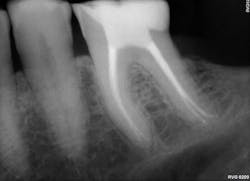

Furthermore, Activa BioActive Bulk Flow provides an option for dentists who appreciate Activa’s bioactive properties but want to work without a dispenser. Activa BioActive Bulk Flow simplifies inventory thanks to ShadeFusion universal color matching. The material is sufficiently radiopaque so dentists can be confident that it will be visible for any clinician evaluating their patient for years to come.